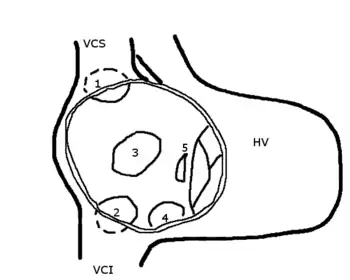

Schematic drawing showing the location of different types of ASD, the view is into an opened right atrium.

HV: right ventricle; VCS: superior vena cava; VCI: inferior vena cava

1: upper sinus venosus defect; 2: lower sinus venosus defect; 3: secundum defect; 4: defect involving coronary sinus; 5; primum defect.

The six types of atrial septal defects are differentiated from each other by whether they involve other structures of the heart and how they are formed during the developmental process during early fetal development.